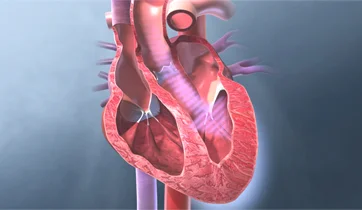

Eisenmenger Syndrome

Actelion Pharmaceuticals, Ltd.

ScienceProd, Paris

Eisenmenger syndrome is caused by a hole in the septum between the left and right ventricles of a baby's heart (ventricular septal defect). The hole allows oxygenated blood to flow back into the lungs, instead of going out to the rest of the body.